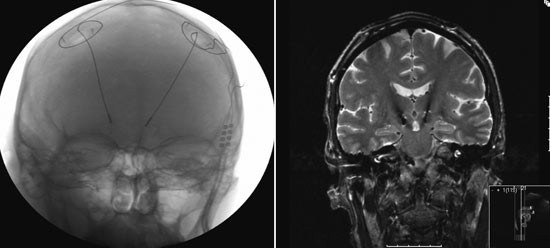

Ved dyp hjernestimulering implanteres elektroder i ulike deler av basalgangliene eller thalamus (fig 1), og kontinuerlig høyfrekvent elektrisk strøm leveres ved hjelp av en implantert eksternt programmerbar pulsgenerator, tilsvarende en hjertepacemaker. Den eksakte virkningsmekanismen er ikke fullstendig klarlagt. Dyp hjernestimulering har imidlertid erstattet lesjonskirurgi fordi denne behandlingen gir en klinisk effekt tilsvarende en lesjon, men uten å skade hjernen permanent og med færre bivirkninger (3). Effekten kan justeres ved hjelp av ekstern programmering av strømfeltets styrke og plassering. I tillegg er det med elektrisk hjernestimulering mulig å påvirke både mindre og dypere strukturer i hjernen enn dem man med rimelig trygghet kunne nå med lesjonsteknikk, slik som nucleus subthalamicus i mesencephalon (fig 2). Et annet betydelig fortrinn er muligheten for bilateral operasjon. Mens bilaterale lesjoner med gammel operasjonsteknikk i mange tilfeller ga permanente nevrologiske utfall, kan man med stimulering kontrollere bilaterale symptomer med lav komplikasjonsfrekvens. Behandlingen kan gi dramatisk og varig bedring av symptomer hos pasienter med ulike bevegelsesforstyrrelser, og disse pasientene har få andre behandlingsalternativer.